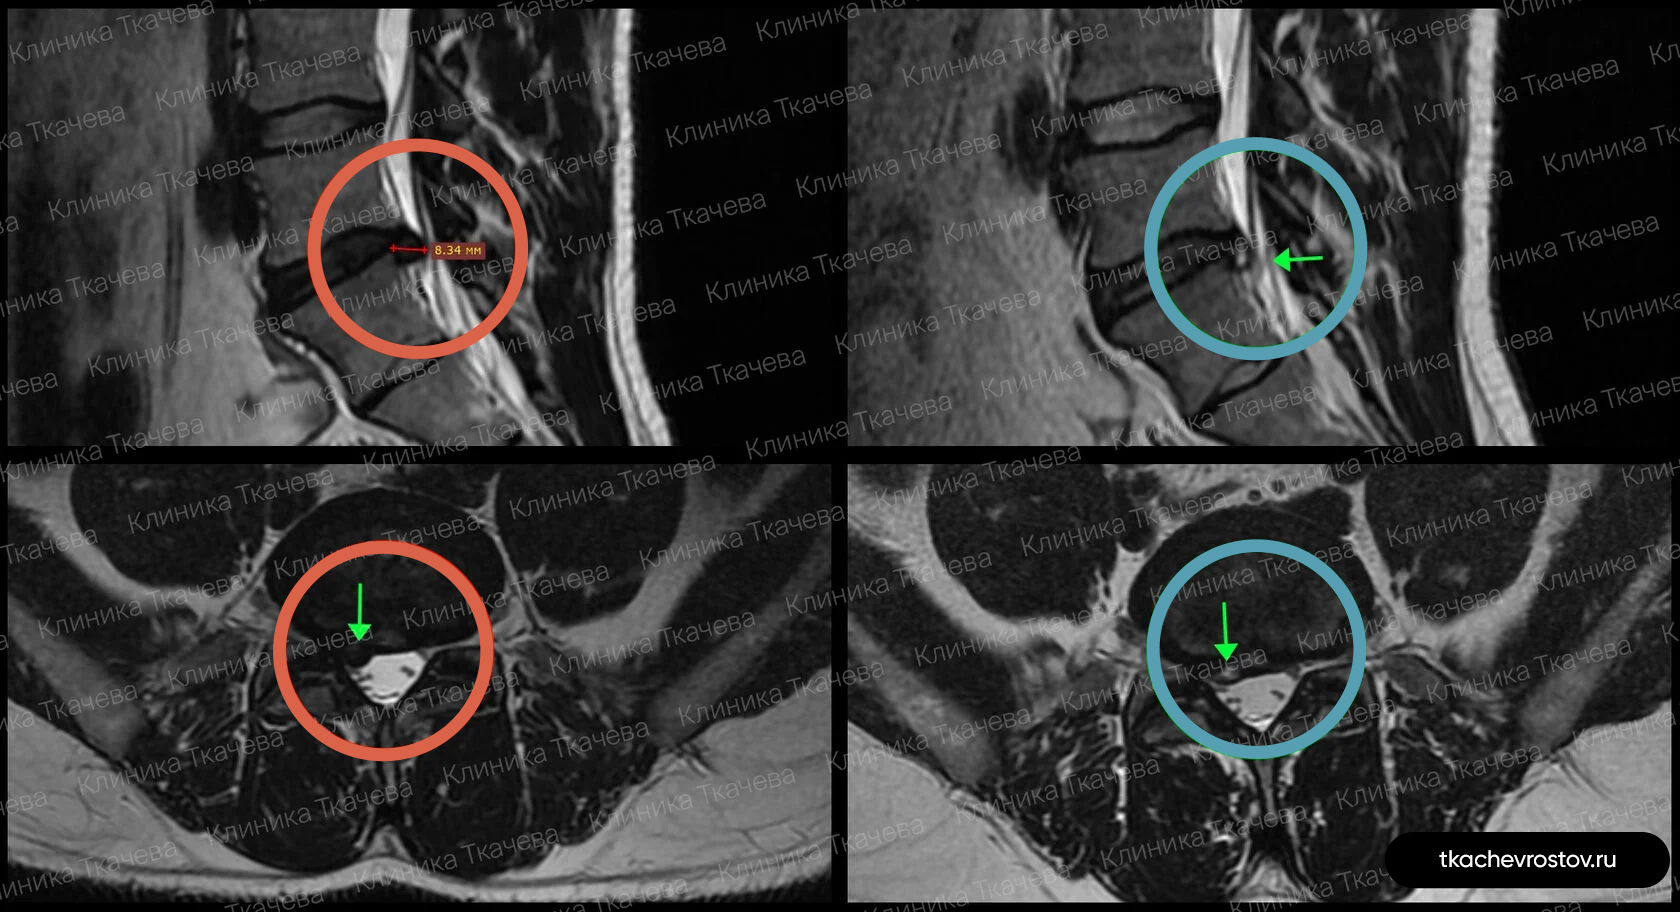

Грыжа в поясничном отделе L5-S1

Мужчина. Секвестрированная грыжа в поясничном отделе L5-S1 1.3 x 3.2 см. Невыносимая боль, хромота и критическое снижение нейропроводимости обеих ног. Никаких альтернатив кроме операции не предлагалось.

ДО:

-

Упражнения с физиотерапевтом и блокады

- Длительная отрицательная динамика

- Невыносимая боль

- Хромота и онемение пальцев ног

- Критическое снижение нейропроводимости обеих ног

- Потеря трудоспособности и ограничение жизнедеятельности

ПОСЛЕ 1 курса:

✓ Наступила полная резорбция грыжи

✓ Наступило улучшения общего состояния

✓ Регрессировали боль и онемение в ноге и пальцах

Пациент прошел 1 курс лечения (12 дней).